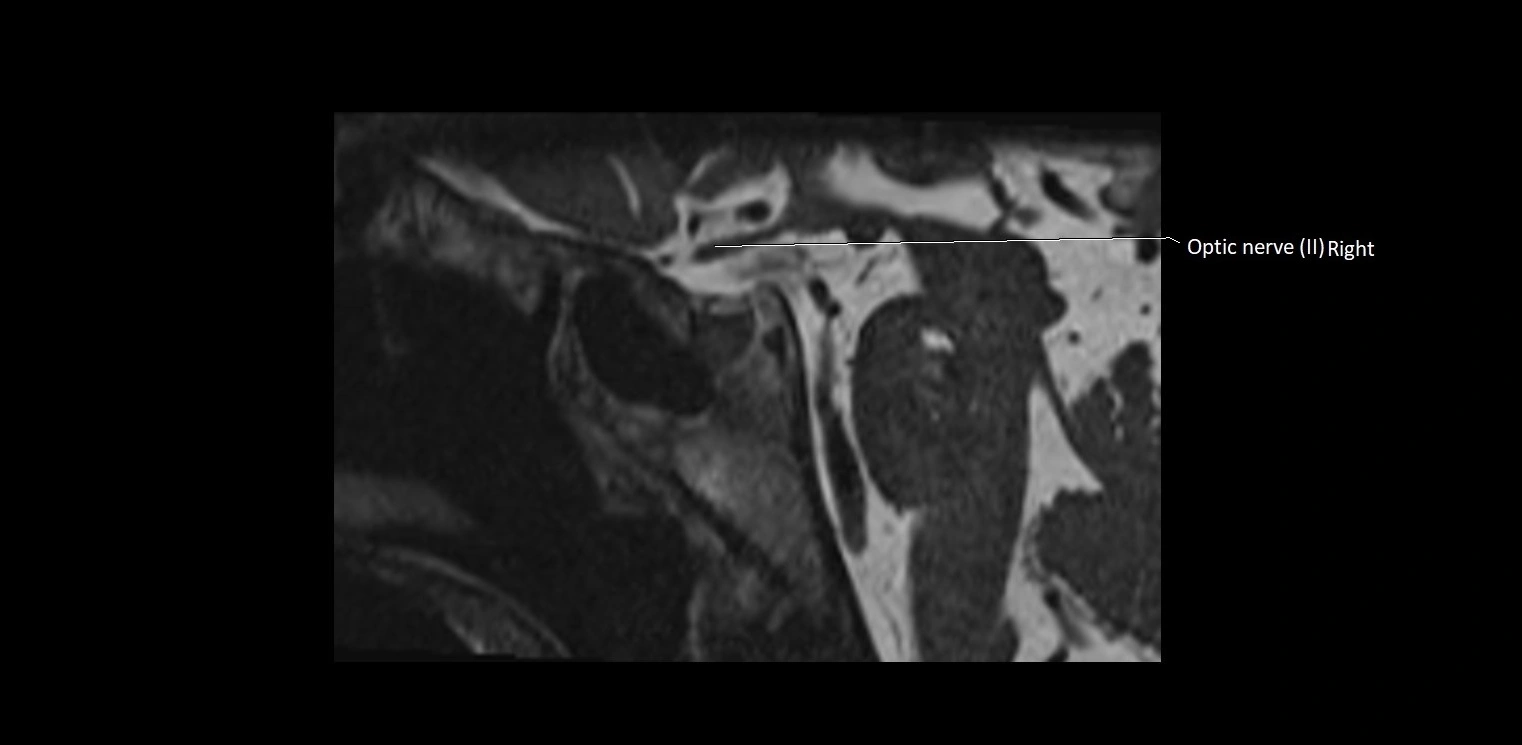

MRI Appearance

• The abducens nerve is a small, thin, linear structure

• Best visualized on high-resolution T2-weighted 3D MRI sequences (e.g., FIESTA or CISS)

• Seen as a hypointense (dark) line running from the brainstem at the pontomedullary junction, traversing the prepontine cistern, and entering Dorello’s canal under the petrosphenoidal ligament, then into the cavernous sinus, and finally the orbit

• May be challenging to visualize in standard MRI due to its small size

• Pathology may be inferred by absence, displacement, or enhancement of the nerve

MRI images

image